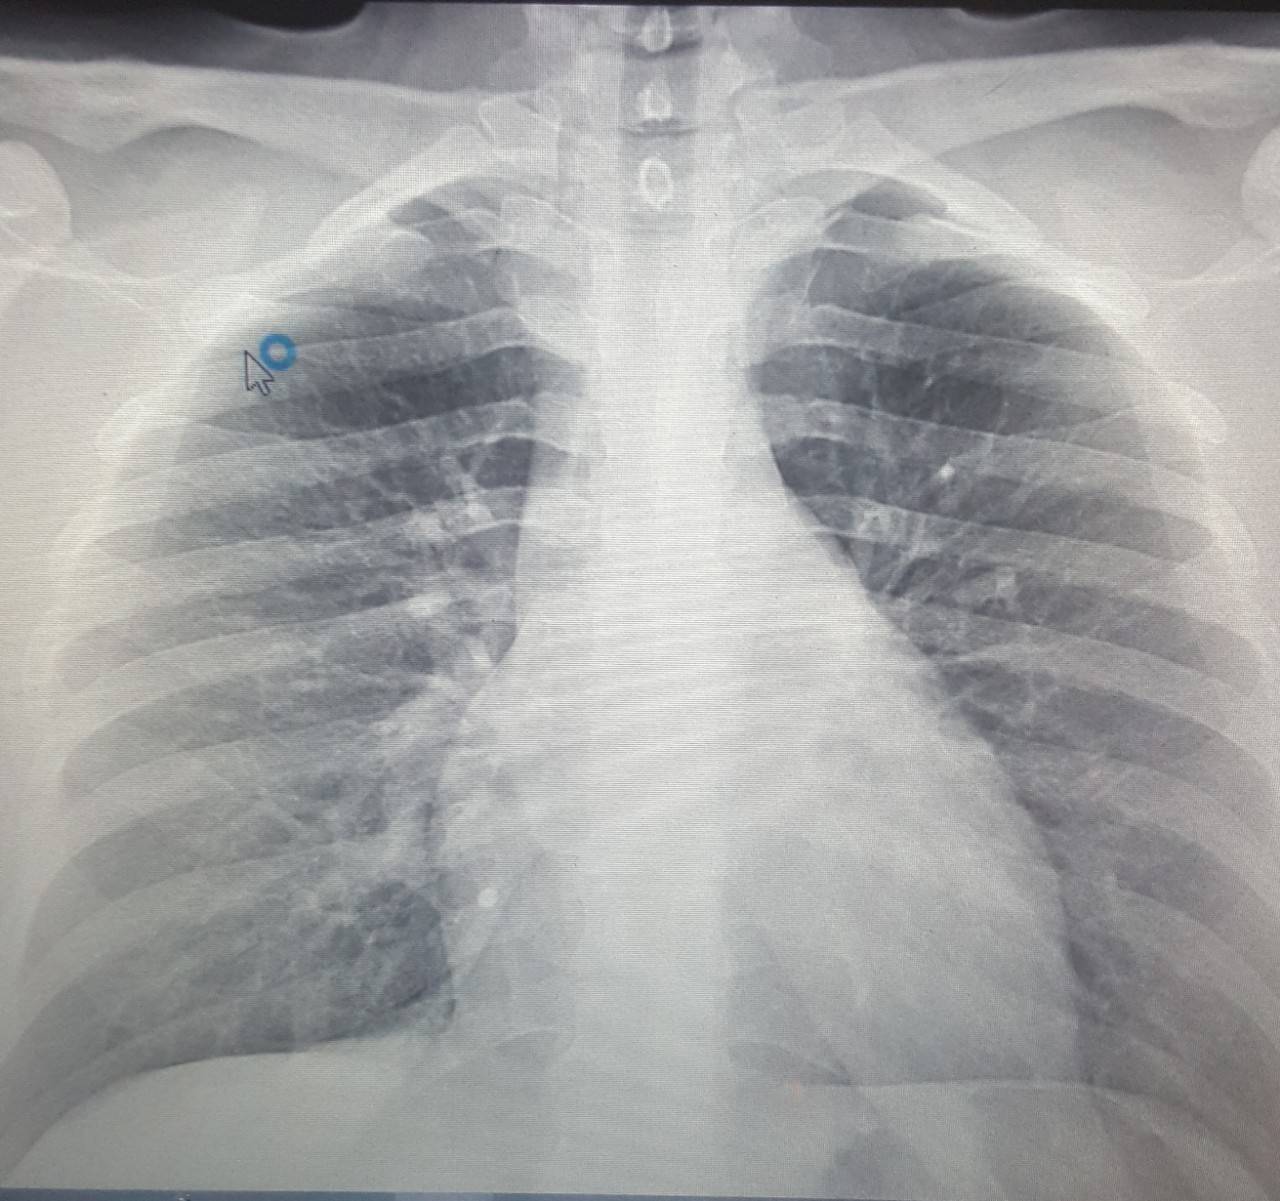

Рентген здоровых легких: примеры снимков и советы

Раздел: Сокровищница опыта